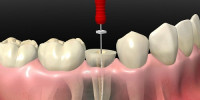

DR NESTOR J GOMEZ GOMEZ - Odontología de Avanzada

DR: NESTOR J. GÓMEZ: dientes perfectos. Consultorio odontologico, Implantologia, Reabilitación, Endodoncia, Periodoncia, Ortodoncia, Cirugia Maxilofacial, Diseño de sonrisa, Implantes, Odontologia Robotica, Escultura Gingival, carillas, lumineers